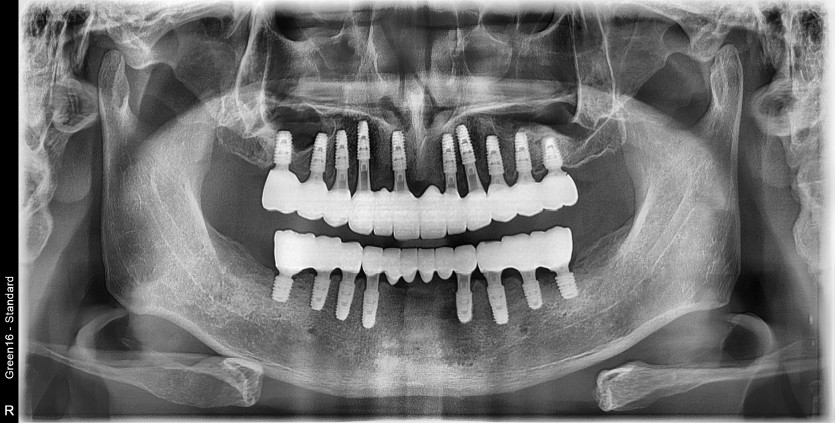

만 50세 전체 임플란트 증례입니다.

전체 임플란트 증례입니다.

18개의 임플란트로 완성하였습니다.